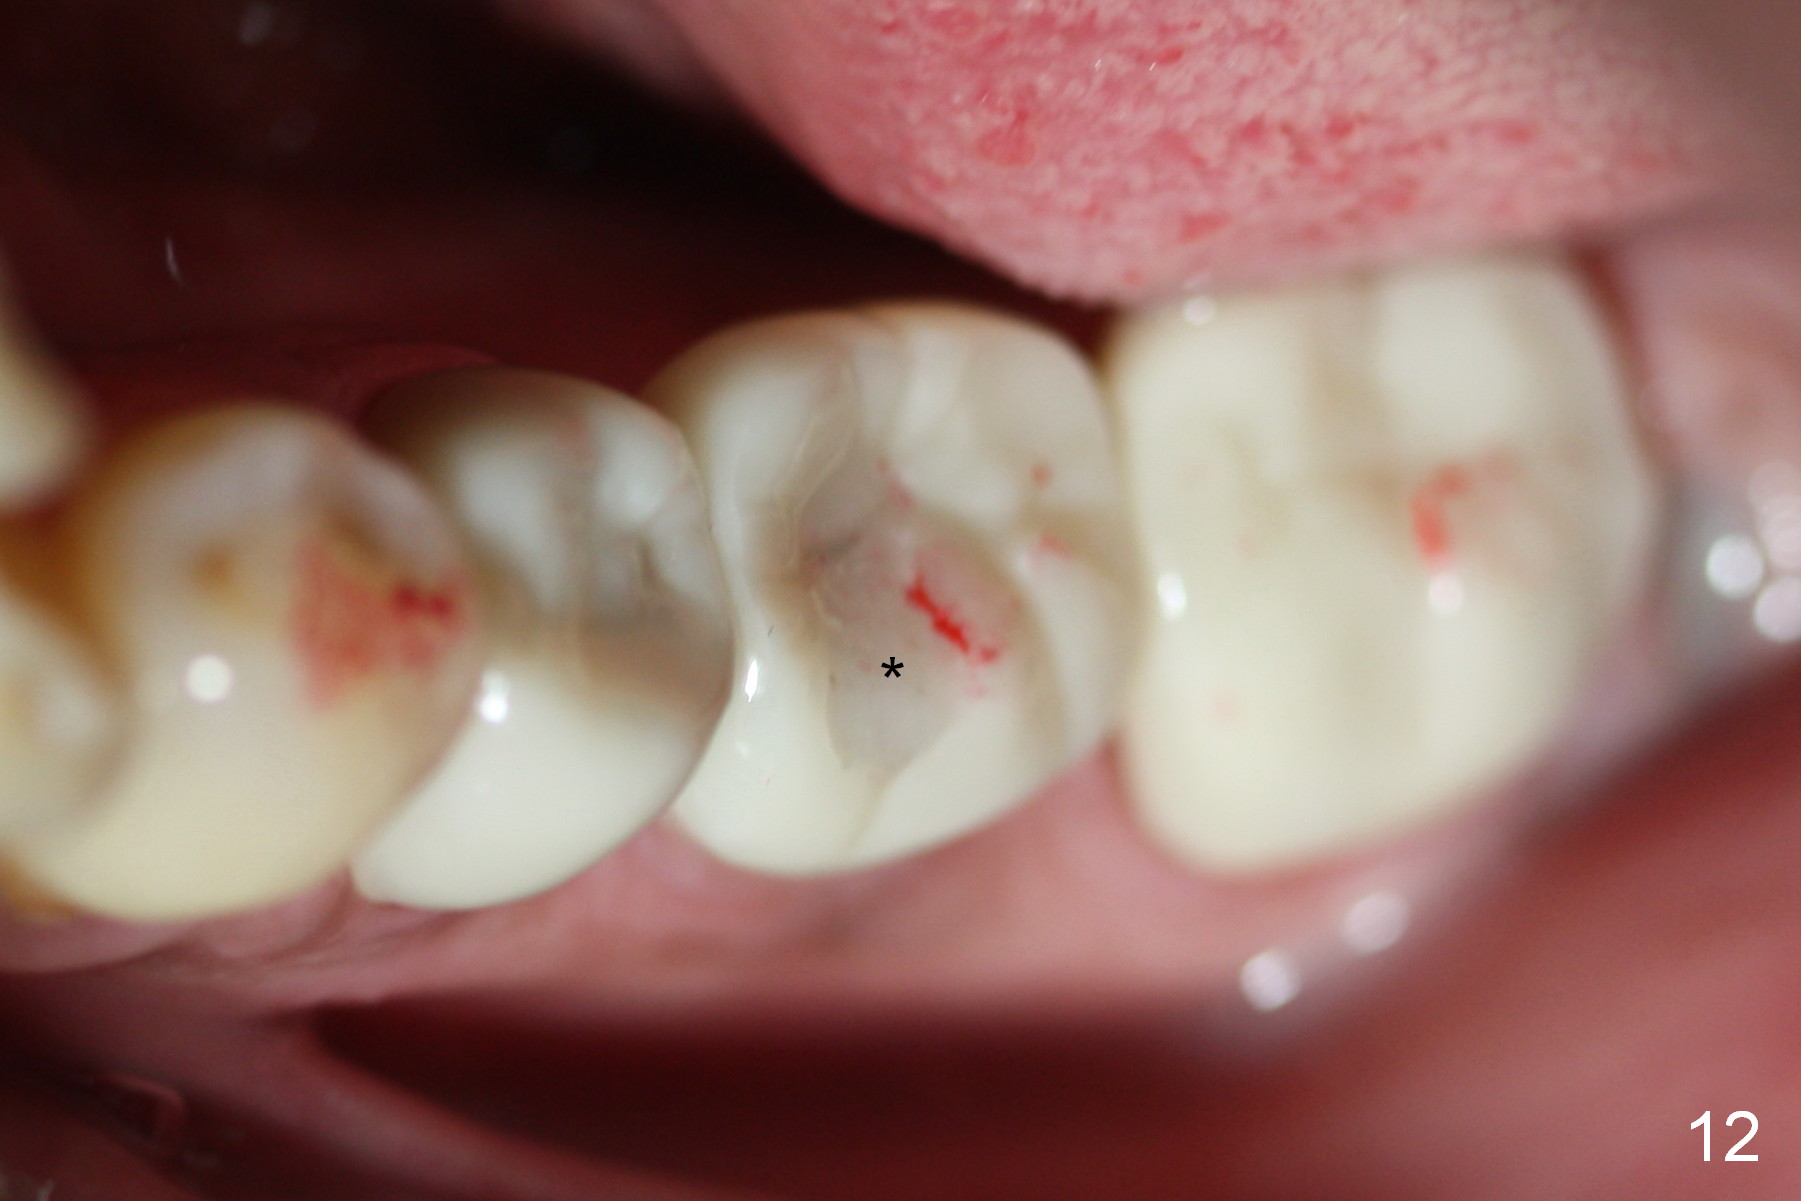

The access is mesial at #19 (Fig.11 v). After cementation, the abutment screw is torqued through the access, which is then closed with flowable composite (Fig.12 *).